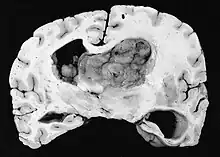

| GFAP stained microscopic section of a subependymal giant cell astrocytoma | |